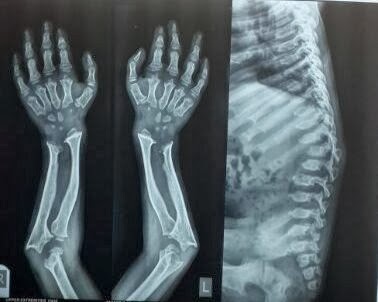

Ap x ray of wrist. Radiograph of the thumb. Trace these arcs on the ap film. Some pathologic processes such as osteomyelitis and arthritis also maybe seen. Normal wrist x ray in an adult female for reference.

See approach to wrist series for more information. X rays of the wrist joint are requested frequently particularly at the emergency assistance department. The wrist and elbow should be at shoulder height which makes radius and ulna parallel lowering the arm makes radius cross the ulna and thus relative shortening of radius. Mri of the shoulder.

The affected arm if possible is flexed at 900 so the arm and wrist can rest on the table. If the arc is broken or there is a widening of a joint space think carpal dislocation. Mri of the elbow. The test is very helpful for detecting the broken bones and dislocated joints.

The standard wrist views are posterior anterior pa and lateral. The spacing between all carpal bones should be 1 2 mm. The wrist comprises the scaphoid lunate triquetrum pisiform trapezium trapezoid capitate and hamate bones. The affected hand is placed palm down on the image receptor.

They are used primarily to confirmexclude a fracture in the diagnostics of rheumatoid arthritis and in functional hand and wrist symptoms. The academic rule of a true lateral wrist radiograph is defined by the pisoscaphocapitate relationship where the palmar cortex of the pisiform should lie centrally between the anterior surface of the distal pole of the scaphoid and the capitate ideally in the central third of this interval 1. The wrist series is comprised of a posteroanterior oblique and lateral projectionthe series examines the carpal bones that are consisting of the scaphoid lunate triquetrum pisiform trapezium trapezoid capitate and hamateit also examines the radiocarpal and distal radiocarpal joint along with the distal radius and ulna. Shoulder elbow and wrist should all be in the transverse plane perpendicular to the central beam.

The radiocarpal distal radioulnar and carpometacarpal joints can also be considered part of the wrist. Ct of the wrist. Wrist hand and fingers. An x ray wrist with both ap and an oblique view is helpful in finding the cause of behind the signs and symptoms of pain tenderness swelling and deformities of the wrist joint.